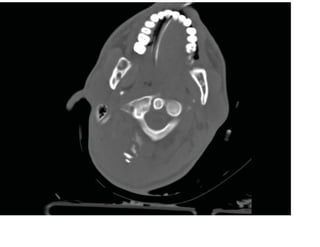

Fenêtres osseuses avec balle logée

Les images tomodensitométriques

axiales des diapositives suivantes

montrent le point d'entrée de la balle

dans le crâne occipital droit avec des

fragments de fracture comminutive.